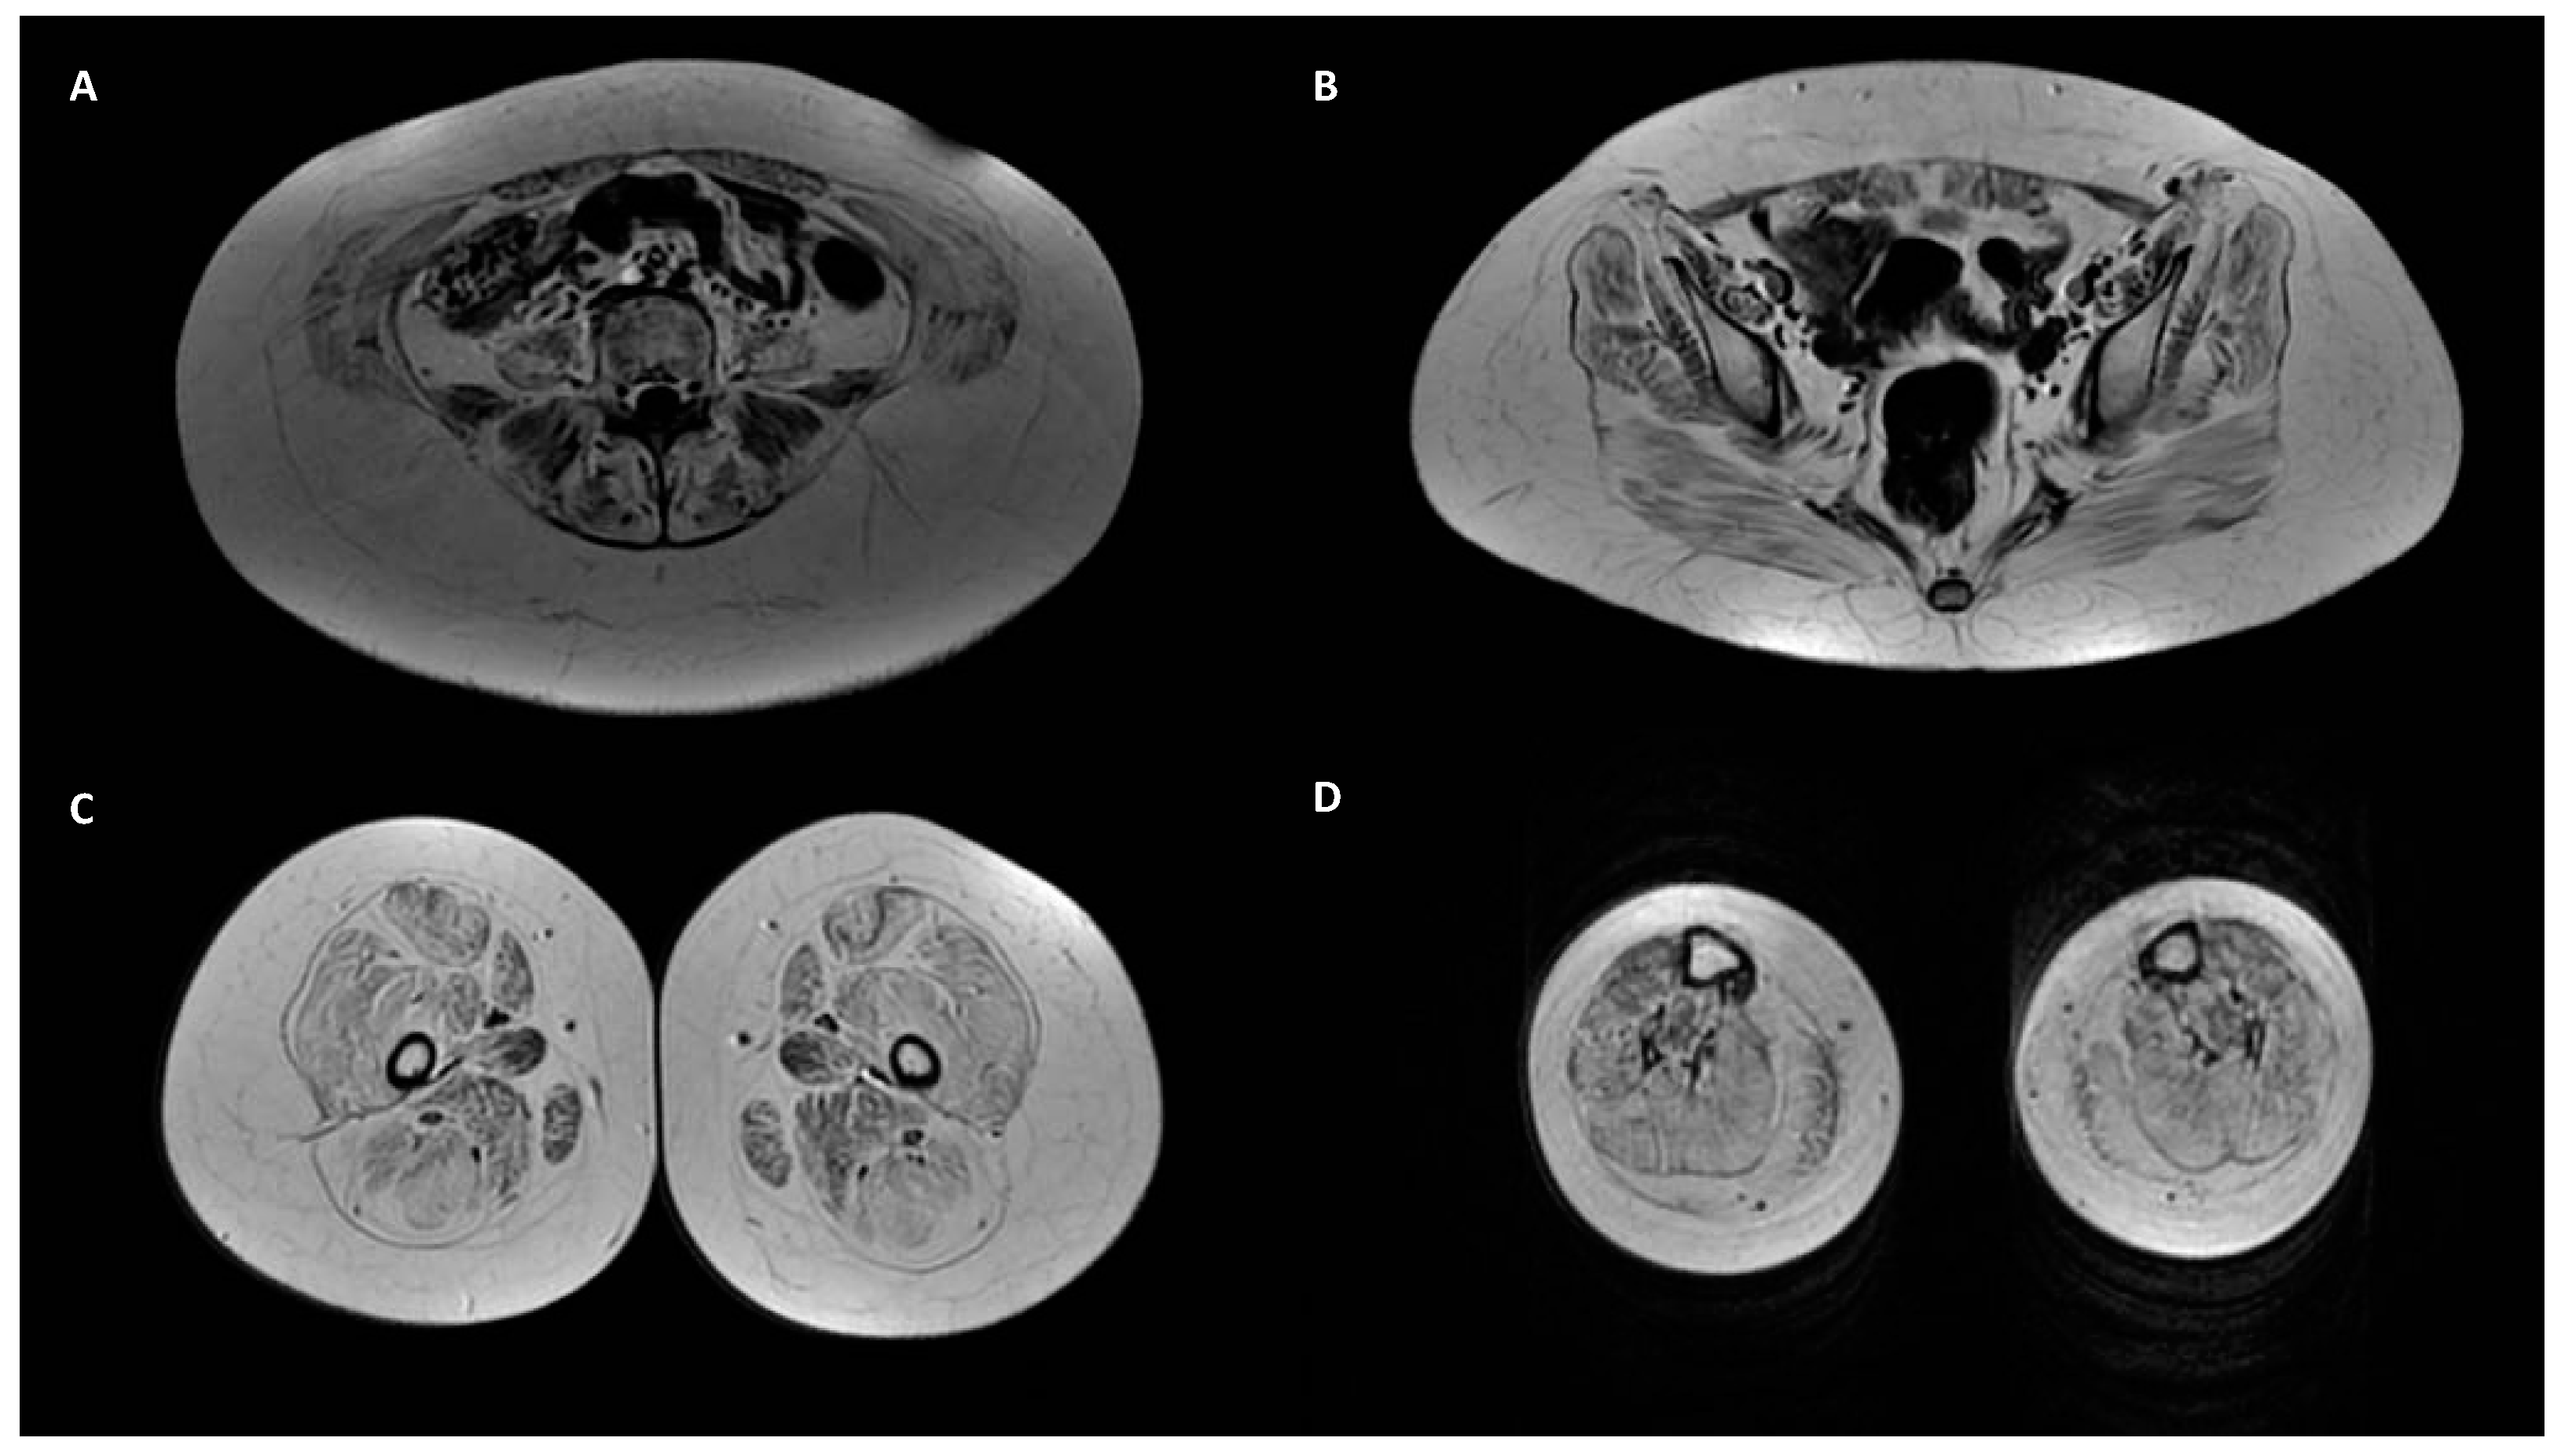

| ID | Age Onset | Gender | Gene | Mutation | CADD-Score | Varsome | Muscle Weakness | Joint Laxity | Contracture or Retraction of Achilleus Tendon | Rigid Spine Scoliosis Hip Alt. | Skin Sign | Lung Alt. | CK Elevation | Muscle Biopsy and COLVI Expression | Skin Biopsy and COLVI Expression | Muscle Magnetic Resonance | Segregation |

|---|---|---|---|---|---|---|---|---|---|---|---|---|---|---|---|---|---|

| 1 | Congenital | F | COL6A3 | c.7176delG: p.G2392fs* homo | 29.2 | Pathogenic | Global (>shoulder and pelvic girdle) | x | x | x | mild | Myopathic sign; COLVI reduction | Reduction | Typical | Father and mother het | ||

| 2 | Congenital | M | COL6A3 | c.7176delG: p.G2392fs* homo | 29.2 | Pathogenic | Global (>shoulder and pelvic girdle) | x | x | x | x | mild | N/A | N/A | N/A | Father and mother het | |

| 3 | 14 | M | COL6A2 | c.1970-9G>A homo | 22.1 | Likely pathogenic | Pelvic girdle | x | x | x | Normal | N/A | N/A | Typical | Father and mother het | ||

| 4 | 58 | M | COL6A1 | c.3013C>T: p.R1005C | 32 | Uncertain significance | Distal muscles of leg | Normal | Myopathic sign | N/A | Normal | N/A | |||||

| 5 | 60 | M | COL6A2 | c.2474C>T: p.A825V | 25.3 | Uncertain significance | Global | Normal | Myopathic sign; COLVI normal | N/A | Normal | N/A | |||||

| 6 | N/A | F | COL6A2 | c.791G>A: p.R264H | 29.3 | Likely Pathogenic | Myalgia, generalized asthenia | x | Normal | N/A | N/A | Atypical | N/A | ||||

| 7 | 44 | M | COL6A2 | c.2461+1G>A | 33 | Pathogenic | Shoulder and pelvic girdle (>pelvic) | N/A | Dystrophic signs | N/A | Typical | N/A | |||||

| 8 | 65 | F | COL6A1 | c.3006C>A: p.H1002Q | 25.2 | Uncertain significance | Distal muscles of arm and leg | N/A | N/A | N/A | N/A | N/A | |||||

| 9 | Congenital | F | COL6A3 | c.6210+1G>A | 34 | Pathogenetic | Global (>shoulder and pelvic girdle) | x | mild | Myopathic sign; COLVI reduction | Normal | N/A | N/A | ||||

| 10 | Congenital | M | COL6A1 | c.842G>A: p.G281E | 27.7 | Likely pathogenic | Global (>shoulder and pelvic girdle) | x | x | x | mild | Myopathic sign; COLVI normal | Intracellular distribution | N/A | N/A | ||

| 11 | 40 | M | COL6A3 | c.2029C>T: p.R677C | 32 | Uncertain significance | Trunk, shoulder and pelvic girdle | severe | Atypical sign | N/A | Atypical | N/A | |||||

| 12 | 13 | F | COL6A2 | c.1358G>A: p.R453H | 29.2 | Likely Pathogenic | Normal | Episodic | N/A | N/A | N/A | N/A | |||||

| 13 | N/A | M | COL6A2 | c.1395+2T>C | 32 | Pathogenic | Normal | severe | N/A | N/A | N/A | N/A | |||||

| 14 | Congenital | F | COL6A2 | c.1806C>G: p.C602T | 27.6 | Uncertain Significance | Global | x | x | x | normal | Myopathic sign; COLVI reduction | Reduction | Typical | Father het | ||

| 15 | 42 | F | COL6A3 | c.4121A>T: p.D1374V | 26 | Uncertain significance | Distal muscles of leg | low | Myopathic sign | N/A | N/A | N/A | |||||

| 16 | 17 | M | COL6A2 | c.2785G>A: p.V929M | 23.4 | Uncertain Significance | Normal | moderate | Myopathic sign; COLVI reduction | Reduction | Typical | N/A | |||||

| 17 | 75 | M | COL6A3 | c.6224C>T: p.P2075L | 24.2 | Uncertain Significance | Right shoulder girdle and orbicular muscles | severe | Atypical sign | N/A | N/A | N/A | |||||

| 18 | Congenital | F | COL6A1 | c.788G>A: p.G263D | 23.9 | Likely pathogenic | Global (>shoulder and pelvic girdle) | x | mild | Dystrophic signs | Reduction | Typical | Parents wt | ||||

| 19 | 6 | M | COL6A1 | c.787G>A: p.G263S | 24 | Likely pathogenic | Myalgia | x | x | severe | Normal | N/A | Normal | N/A | |||

| 20 | 4 | F | COL6A3 | c.2845G>A: p.A949T | 24.2 | Uncertain Significance | Normal | moderate | Myopathic sign | N/A | N/A | N/A | |||||

| 21 | Congenital | F | COL6A3 | c.8359G>A: p.A2787T | 23.4 | Uncertain Significance | Shoulder and pelvic girdle | x | x | x | normal | Myopathic sign | N/A | Normal | N/A | ||

| 22 | 4 | F | COL6A3 | c.8009C>T: p.A2670V | 23 | Likely pathogenetic | Orbicular muscles | normal | Atypical sign | N/A | Normal | N/A | |||||

| 23 | 60 | F | COL6A1 | c.2635A>G: p.S879G | 23 | Uncertain Significance | Trunk, shoulder girdle and facial muscles | moderate | Myopathic sign | N/A | N/A | N/A | |||||

| 24 | 40 | F | COL6A2 | c.2182G>A: p.V728M | 24.8 | Uncertain Significance | Myalgia | severe | Atypical sign | N/A | Normal | N/A | |||||

| 25 | Congenital | F | COL6A1 | c.1315C>T: p.R439W | 23.7 | Likely pathogenic | Trunk, shoulder and pelvic girdle | x | x | x | Normal | Normal | Reduction | Normal | Mother het | ||

| 26 | Congenital | F | COL6A3 | c.787G>A: p.D263N | 23.5 | Uncertain Significance | Pelvic girdle | x | x | x | Normal | N/A | Reduction | Normal | Father het | ||

| 27 | Congenital | M | COL6A2 | c.2950G>A: p.V984M | 23.2 | Uncertain Significance | Pelvic girdle | x | Normal | N/A | Normal | Atypical | Father het | ||||

| 28 | 11 | M | COL6A2 | c.2991C>G: p.F997L | 24.8 | Uncertain Significance | Pelvic girdle (ptosis) | Mild | Myopathic sign; COLVI normal | Reduction | Normal | Parents wt | |||||

| 29 | 30 | M | COL6A3 | c.2212A>T: p.R738W | 24.8 | Uncertain Significance | Global (ptosis) | x | Mild | Inflammatory signs | N/A | Atypical | N/A | ||||

| 30 | 40 | M | COL6A3 | c.7258C>T: p.R2420W | 23.3 | Uncertain Significance | Shoulder and pelvic girdle | x | x | Severe | Dystrophic signs | N/A | N/A | N/A |